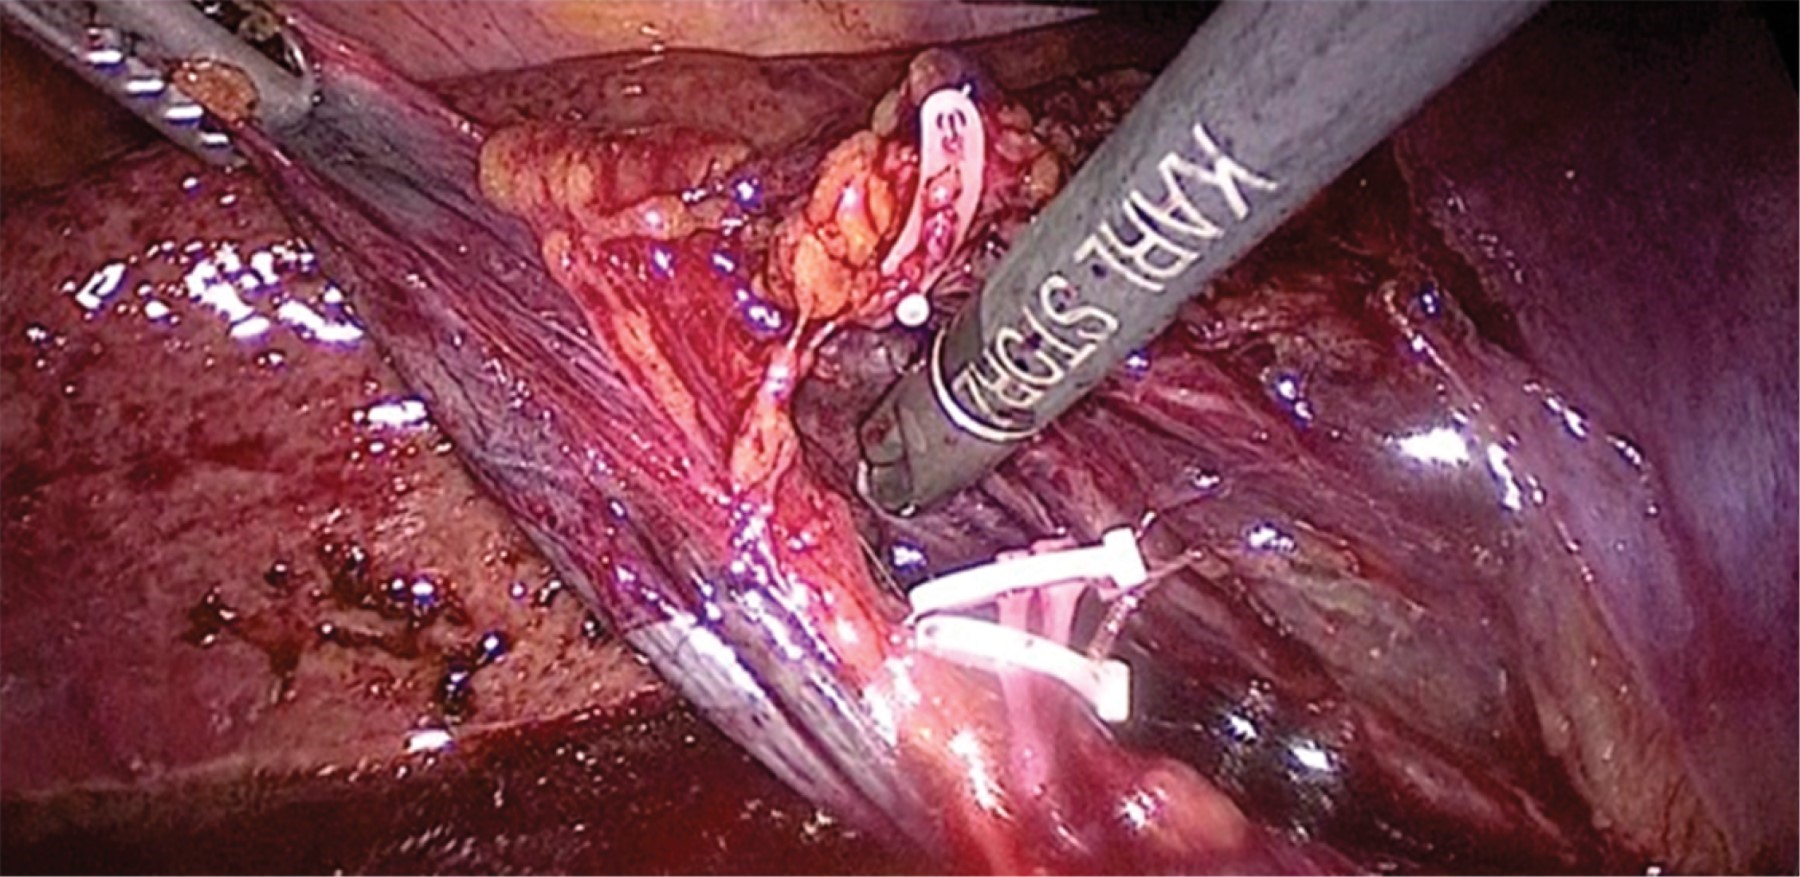

Bajo anestesia general, se colocó al paciente en posición americana; se realizó neumoperitoneo por puerto de 12 mm transumbilical con técnica abierta; se colocó, bajo visión directa, puerto de 10 mm subxifoideo y dos puertos de trabajo de 5 mm; se llevó a cabo laparoscopia diagnóstica que encontró vesícula biliar perforada, hemoperitoneo y sangrado activo intravesicular (Figura 3); se ejecutó aspirado de hemoperitoneo y bilis; se efectuó tracción cenital de vesícula biliar y disección de arteria cística; se practicó clipado con Hem-O-Lok® en arteria y conducto cístico, previa vista crítica (Figura 4); se resecó vesícula biliar con bisturí armónico; se retiró pieza quirúrgica utilizando bolsa endoscópica; se hizo lavado de cavidad y aspirado; se colocó Surgicel® en lecho quirúrgico y drenaje tipo Blake 19 Fr; se retiraron puertos de trabajo, bajo visión directa, sin evidencia de sangrado; se afrontó aponeurosis y piel; y se dio por concluido el acto quirúrgico; por último, se reportaron 1,000 ml de sangrado y un tiempo quirúrgico de 100 minutos. El paciente presentó buena evolución postquirúrgica, toleró la vía oral en el segundo día y se decidió su egreso en el quinto día postquirúrgico. Reporte de patología: vesícula biliar con colecistitis aguda perforada con necrosis transmural, no se observan datos de malignidad.

Figura 4